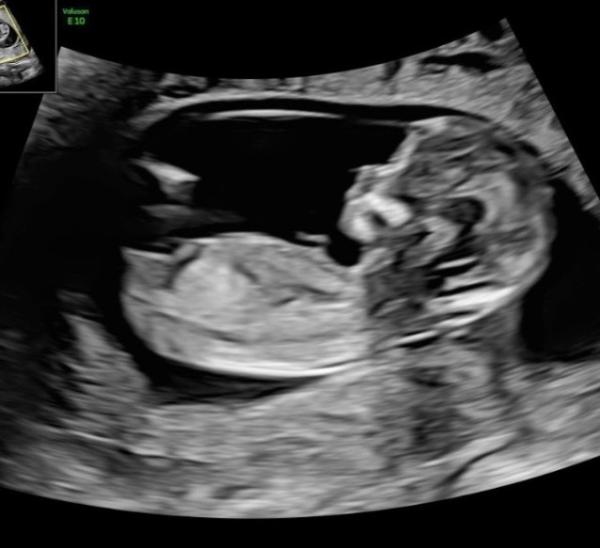

Hallo Mädels, wer kennt sich denn damit aus? Hatte eine von euch bei der Nackenfaltenmessung vielleicht eine ähnliche Erscheinung des Nubs und bereits ein Outing? Natürlich ist ein gesundes Kind das wichtigste aber spekulieren darf man ja

Bild zu Frage an alle Nub-kenner - Forum für Juni - Mamis